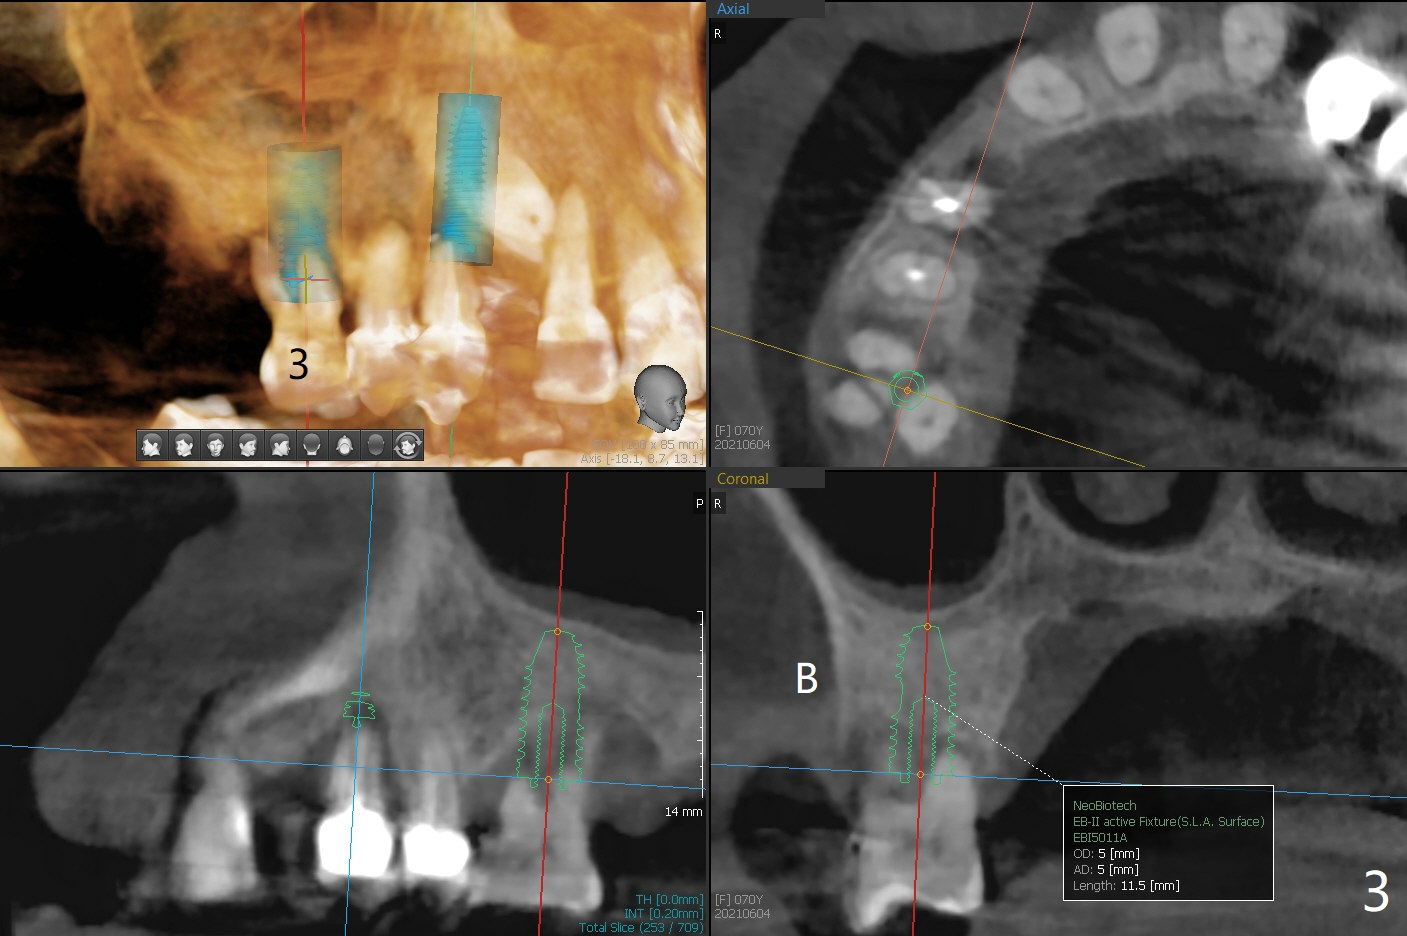

A 70-year-old woman requests implants at #3 and 5 because of bone loss (Fig.1). Since the impacted tooth #6 crosses the trajectory of the implant at #5, extraction of the former is necessary (Fig.2). Palatal bone loss is severe at #5, a 3.5x15 mm 1-piece implant will be placed slightly more buccal than what is shown for 4x13 mm 2-piece one at Fig.2. A 5x11.5 mm implant will be placed at #3 without sinus lift (Fig.3). In fact the patient is concerned about cleasenability of the cantilever bridge. One-piece implant will be placed if needed (Fig.4).